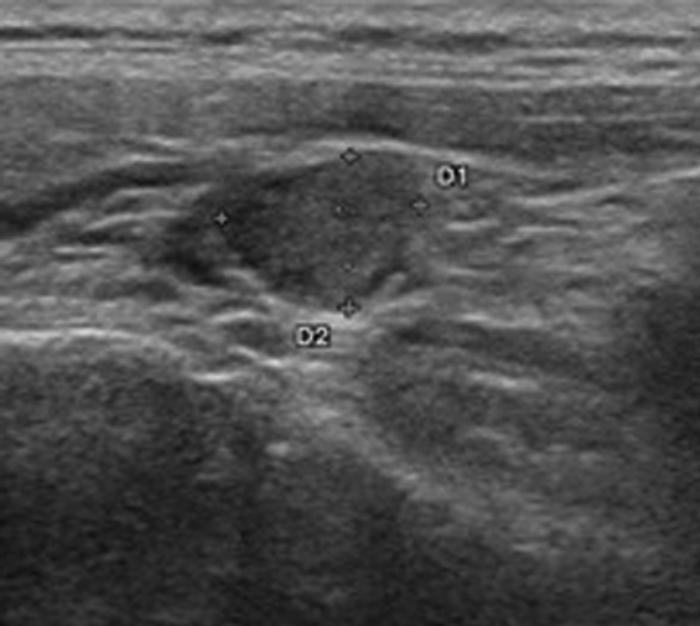

Ultrasound (US) has excellent spatial resolution and is radiation free but is highly operator dependent and as such has a wide range of reported sensitivities and specificities [7]. The typical appearance is of a homogenously hypoechoic well defined mass which has prominent vascular supply on Doppler interrogation (Figure 3). Whilst the technique is useful for assessment of adenomas in expected areas, lesions in the tracheoesophageal groove, retro-oesophageal region, mediastinum or lesions within the thyroid are particularly difficult to assess. In order to maximise lesion identification US is often combined with scintigraphy either using both in the first instance or reserving the latter for patients with a negative ultrasound [8].

Figure 3: Ultrasound demonstrating a well defined hypoechoic lesion (top) with a prominent vascular supply on the Doppler images (bottom) consistent with an adenoma.